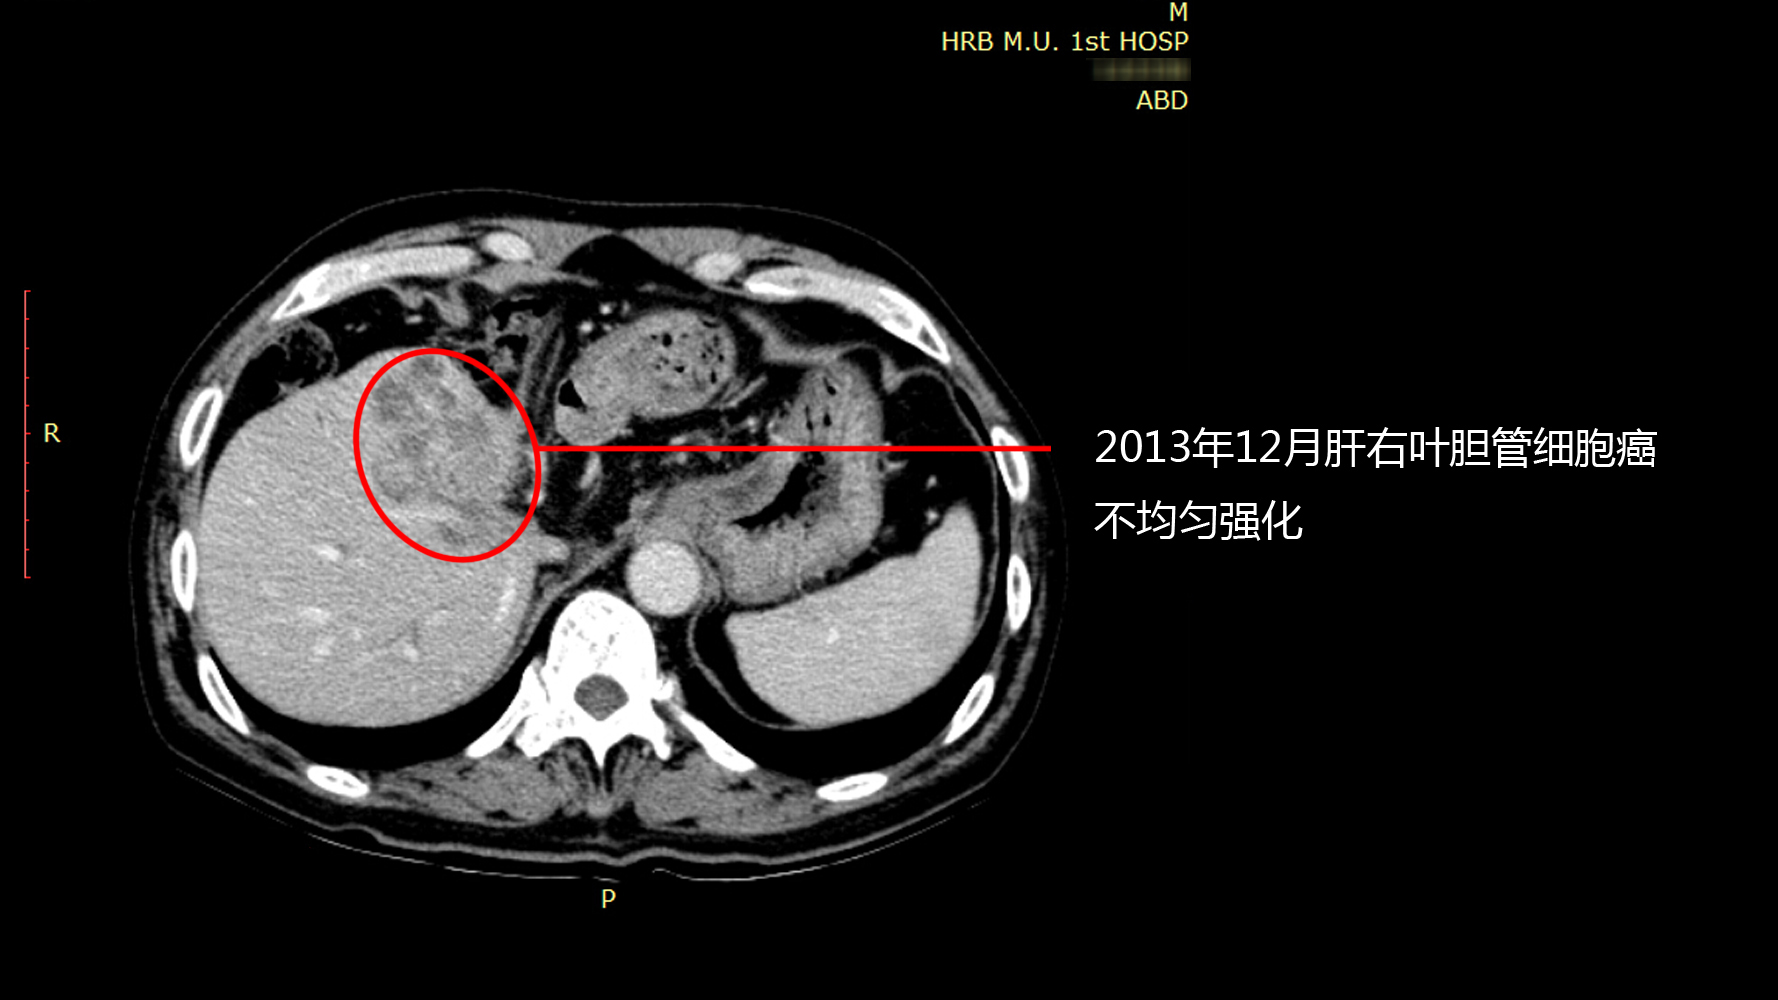

质子治疗前

2013年12月CT显示:肝右叶胆管细胞癌不均与强化。